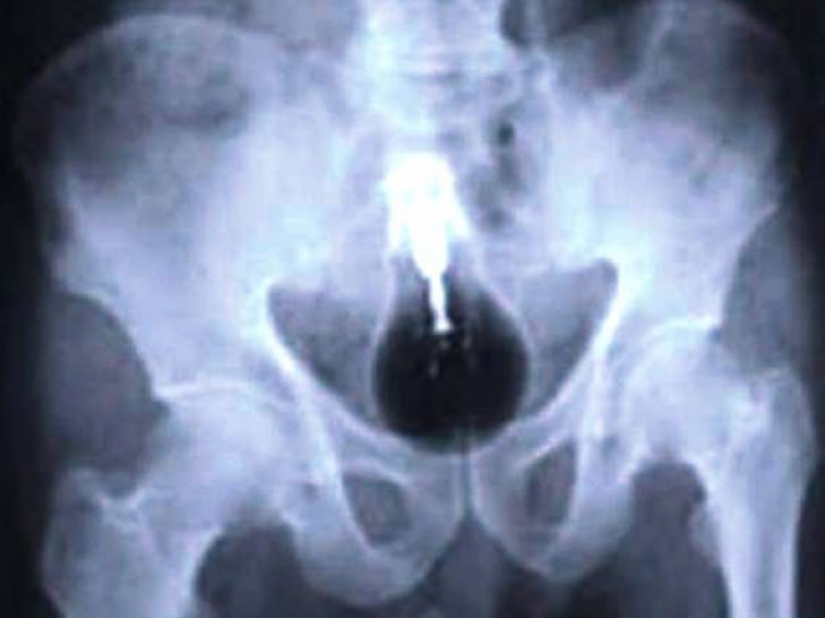

And it looks like the man who swallowed a considerable quantity of drugs to carry their contraband across the border.